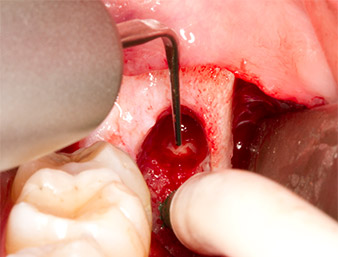

Dopo l'anestesia tronculare e l'anestesia locale, il sito operatorio è stato aperto e il tessuto molle esposto per l'accesso retromolare boccale (Fig. 3).

Il tessuto al di sopra del residuo di radice non era completamente ossificato ed era costituito per la maggior parte da tessuto di granulazione modificato dall'infiammazione (Fig. 4).